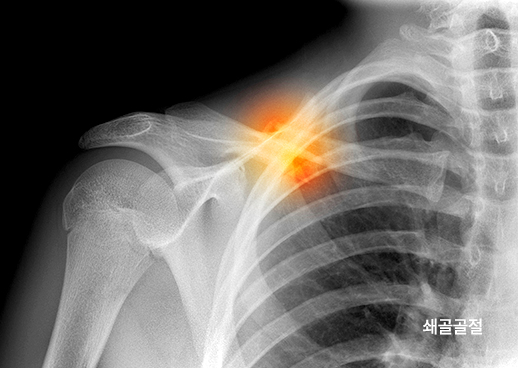

어깨골절은 쇄골골절과 상완골두·경부골절로 구분됩니다. 쇄골골절은 어깨의 지지대 역할을 하는 쇄골의 골절을 말합니다. 상완골두·경부골절은 상완골의 골두나 경부에 발생한 골절로, 대부분 수술적 치료가 필요합니다.

톨리드정형외과는 환자의 골절 부위와 상태를 정확히 평가하여, 수술적 치료가 필요한지 비수술적 치료가 가능한지 정확히 판단합니다.

어깨골절 수술은 쇄골골절과 상완골두·경부골절로 나뉘며, 각각 수술 방법과 회복 과정이 다릅니다. 톨리드정형외과는 환자의 골절 부위와 상태를 면밀히 평가하여, 가장 적합한 수술 방법을 결정합니다.